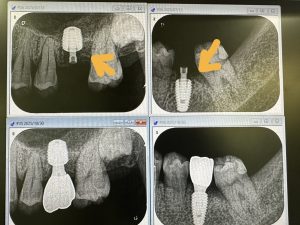

今後の観察は、左上下6.7番隣接の骨が如何に増えるか!?動揺はだいぶ減少している💪

EMDにCGFメンブレン使用(再生治療)